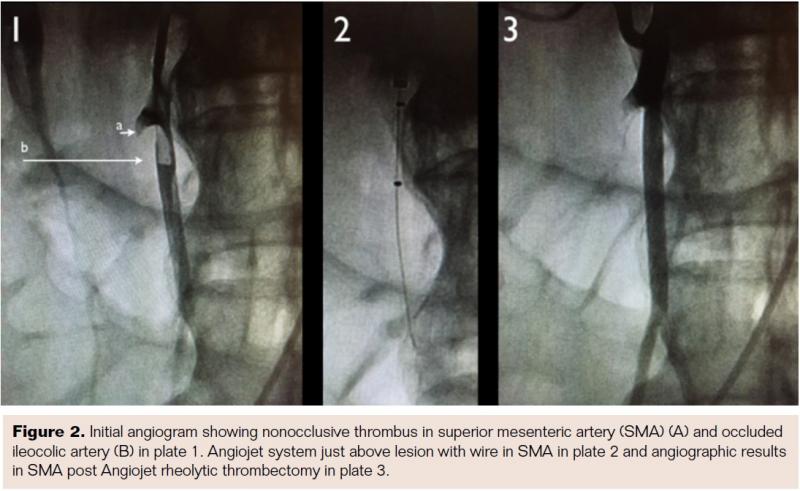

The patient was taken for urgent angiography due to rapid rise in biomarkers reflecting early bowel necrosis. Right femoral artery access was obtained and cannulated with a 6 Fr sheath. A 4 Fr internal mammary catheter was used to cannulate the superior mesenteric artery (SMA). The catheter was advanced into the proximal segment of the vessel over a Glidewire (Terumo). Angiography via the internal mammary catheter confirmed the CT angiographic findings. This catheter was exchanged for a 6 Fr, 55 cm Ansel guiding sheath (Cook Medical). Activated clotting time was 177 seconds, and heparin 3,000 U bolus was administered intravenously. A 0.014˝ wire was advanced through the occluded distal SMA and thrombectomy was done using an Angiojet XVG thrombectomy catheter with complete resolution of the thrombus (Figure 2). The wire was then advanced into the ileocolic artery, which was treated with a similar technique (Figure 3). The proximal segment of the ileocolic artery showed thrombus resolution but a large branch of this vessel was still occluded. Thrombectomy in this branch did not re-establish flow in the vessel, and the angiographic appearance was consistent with diffuse spasm. A 135 cm Cragg-Mcnamara Valved Infusion Catheter (Medtronic) with 10 cm infusion length was then advanced into this branch (Figure 4) and intra-arterial papaverine was administered via this catheter at 30 mg/hr. An intravenous heparin drip was administered peripherally at 500 U/hr.